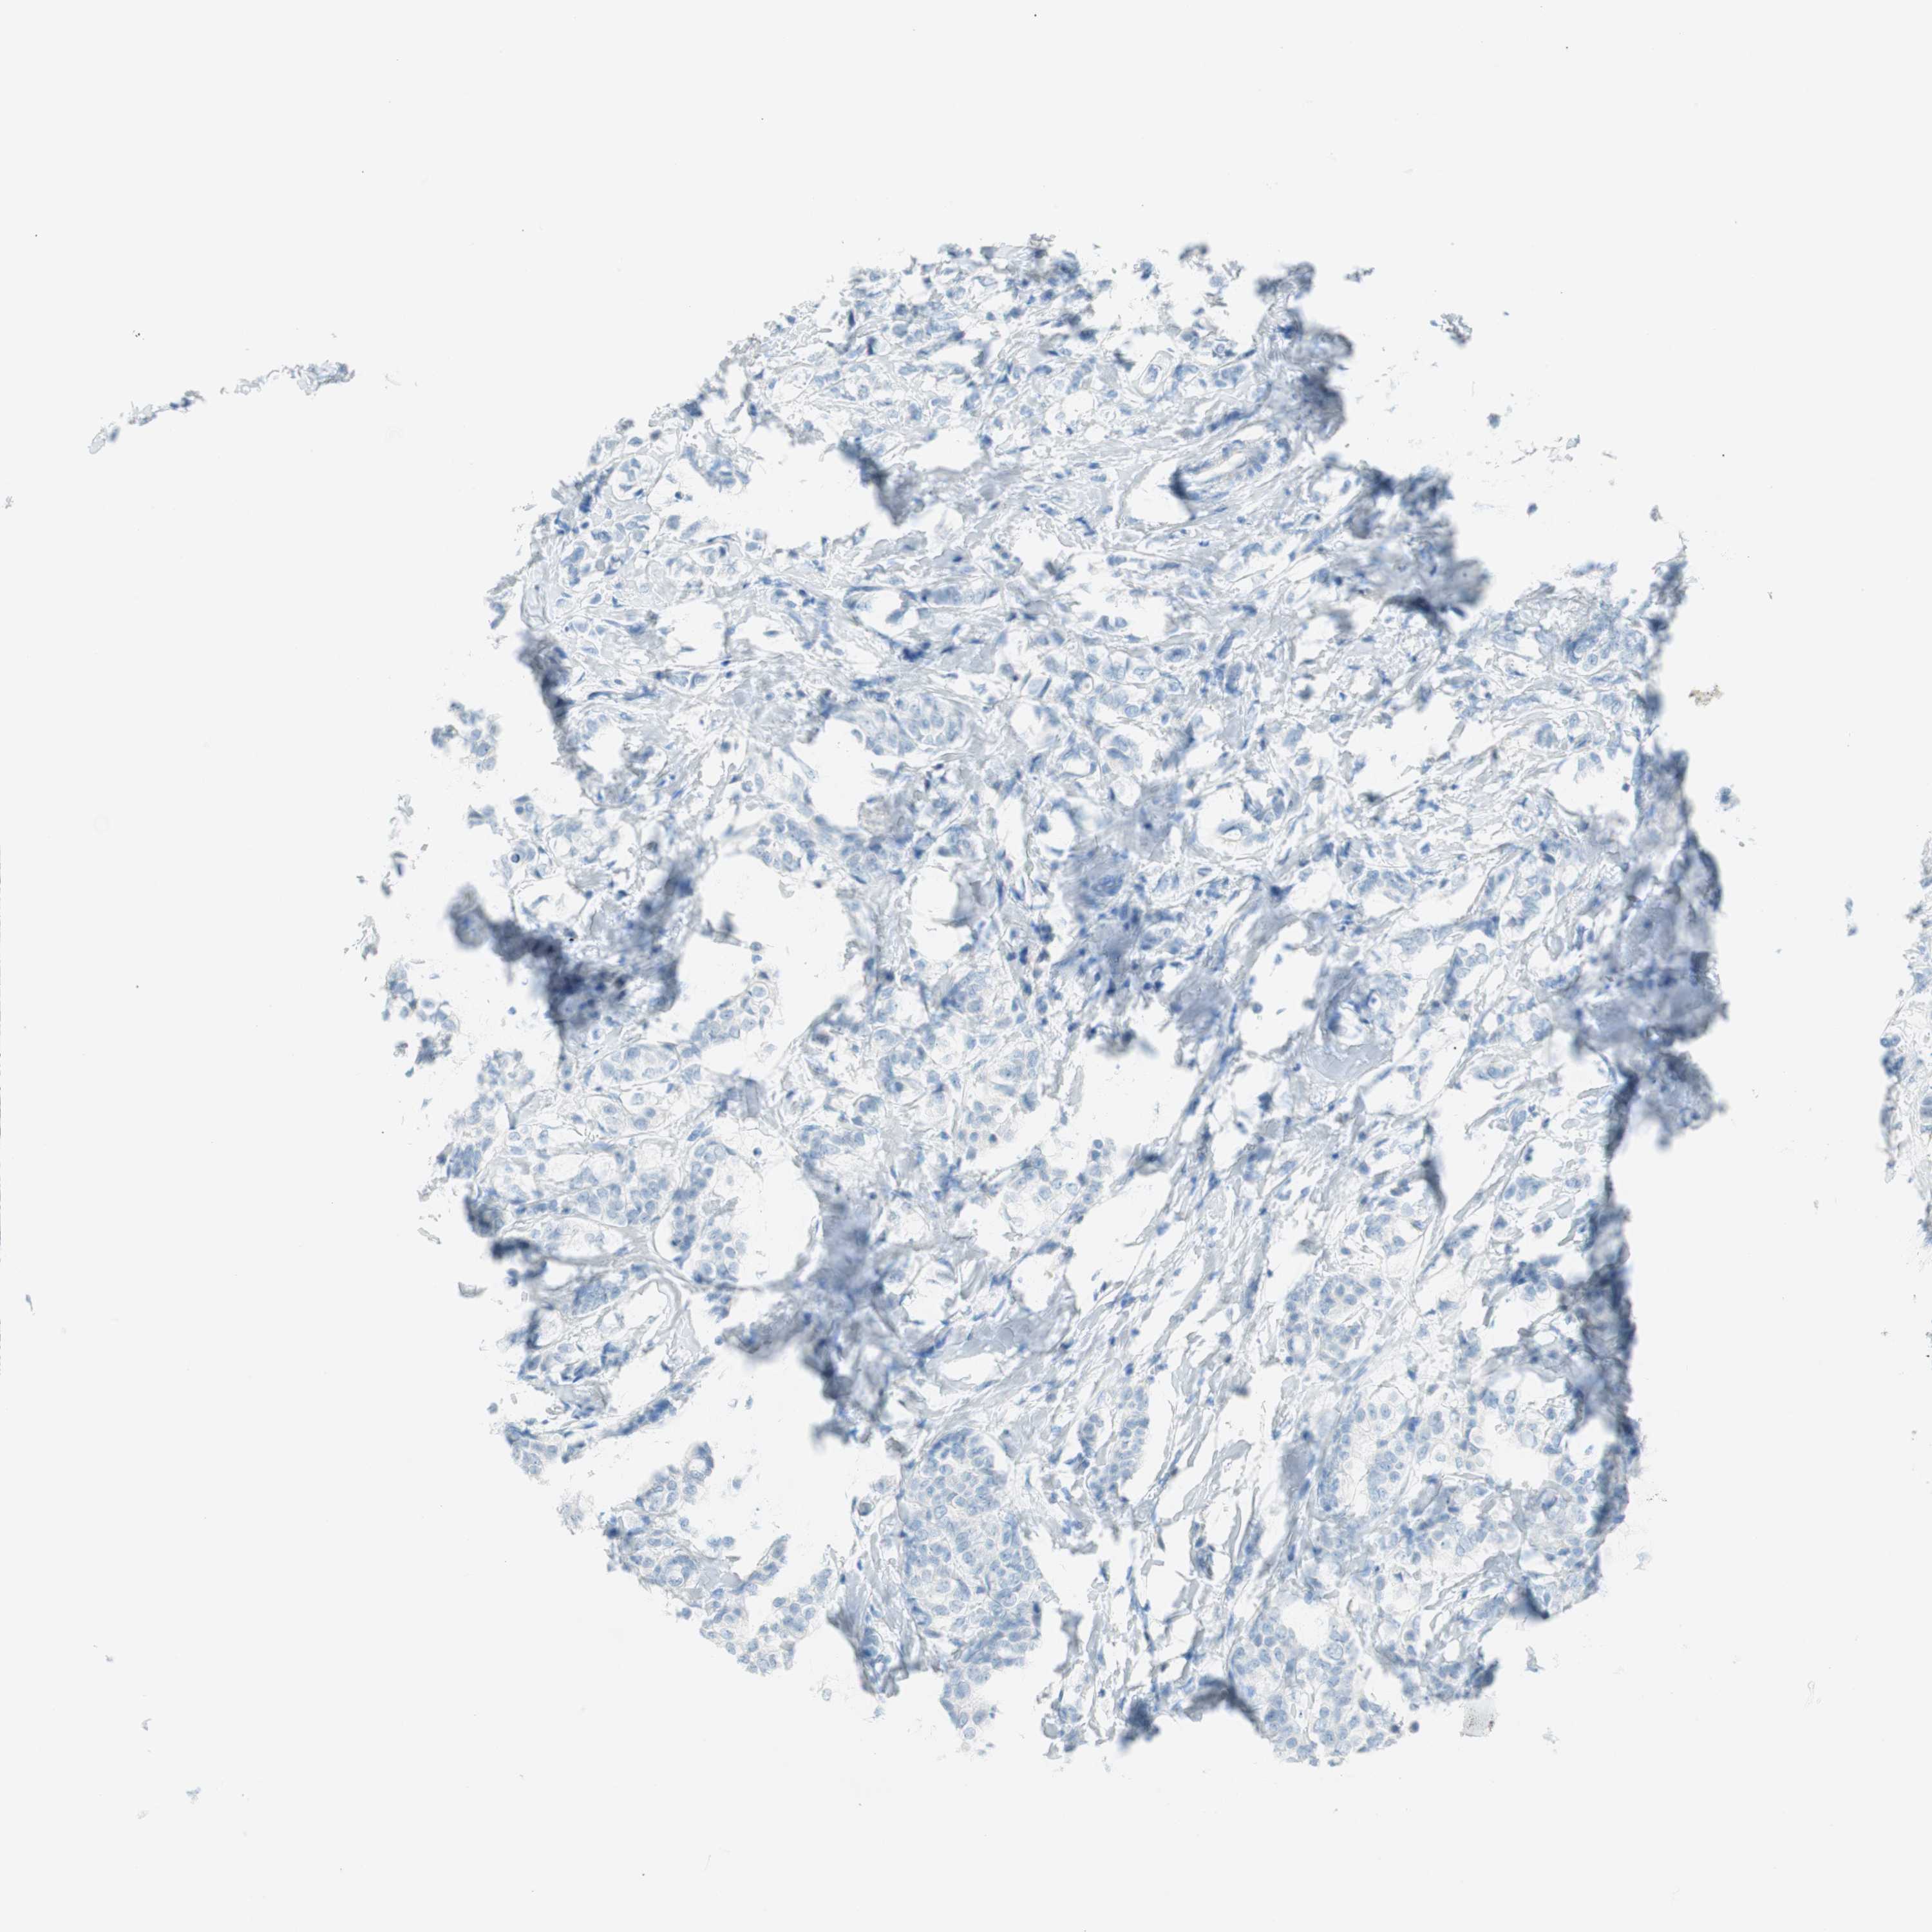

BRCA TCGA BRCA VALIDATION PROTEIN EXPRESSION

ANTIBODIES

AND

VALIDATION